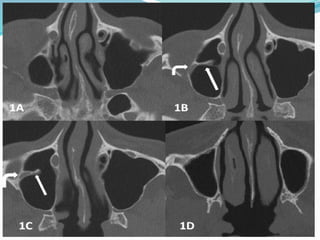

• #73 Axial CT scan slices, from top to bottom. A. Upper part of the maxillary sinus.B,C, slightly below A: the septum (straight arrow ) starts from the lateral sinus wall. Within it the infraorbital nerve (curved arrow) .D: lower portion of the sinus , without septum. CT parameters in both cases were the following: 64 slices MDCT , 0625 mm thin slices, 100 kV, 50 mA resulting in patient 1 in a CTD/vol of 2,74 mGy, DLP 37,5 mGycm and 1,5 mSev